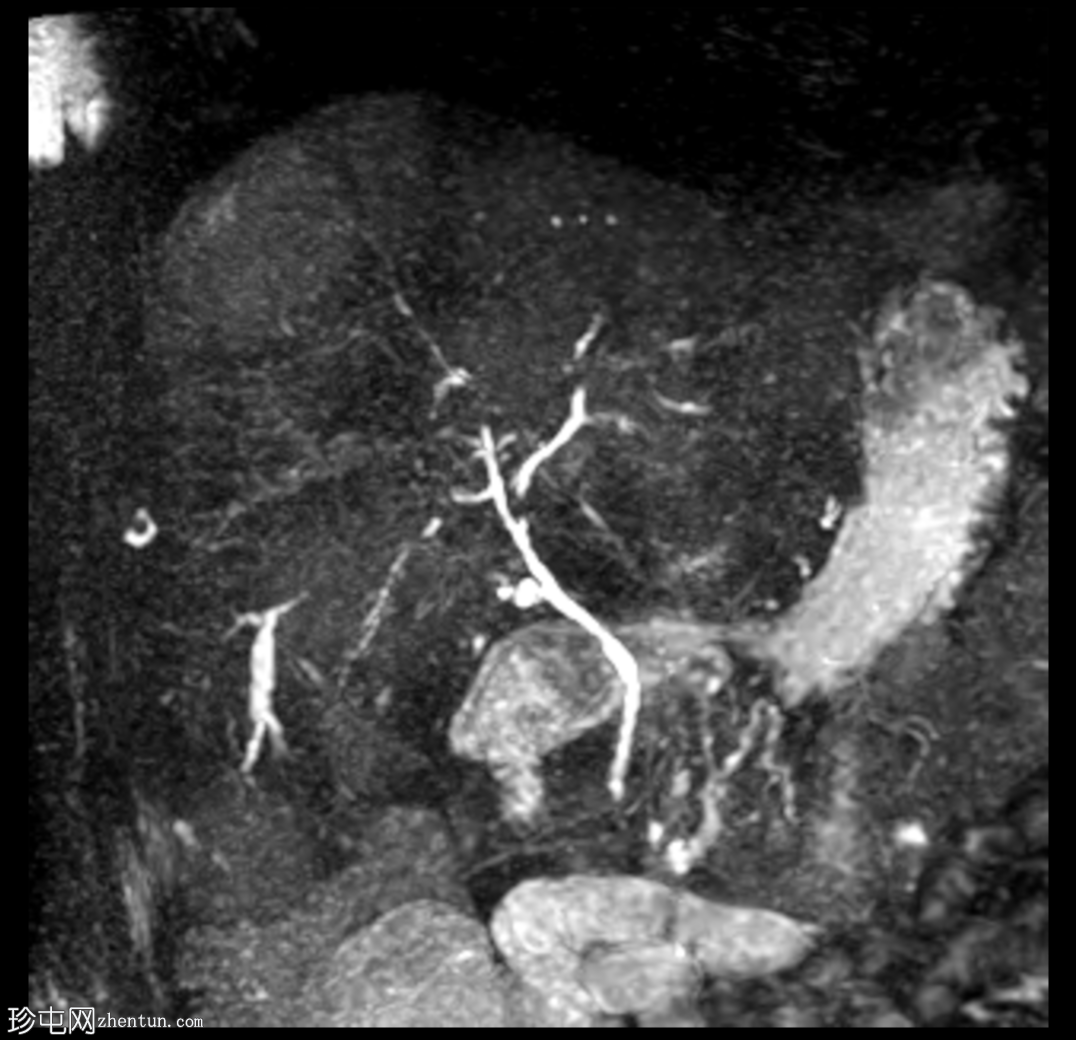

冠状位

MIP、MRCP

肝脏多发病灶,其中数个病灶呈中心T2高信号。

磁共振胰胆管造影(MRCP)显示肝转移灶处存在多处短段胆管狭窄和闭塞,上游胆管扩张,提示

肿瘤

直接压迫/浸润。

肝总管(CHD)和胆总管(CBD)通畅,管径正常。

无胆总管结石。

肝转移灶中心T2高信号最可能是由于肿瘤快速生长导致的中心坏死。

与转移性胆管癌相比,恶性胆道梗阻在胆管癌中更为常见。